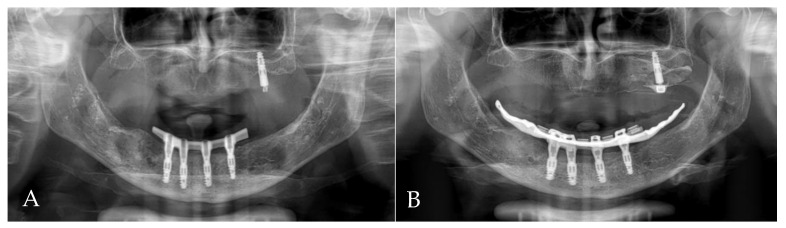

Follow-up clinical photographs: (A–C) 4 months after first surgery—the prosthetic restoration’s finalization; (D,E) 24 months after bar-retained overdenture delivery.

Orthopantomogram (OPG): (A) 4 months after first surgery—the prosthetic restoration’s finalization; (B) 24 months after bar-retained overdenture delivery.